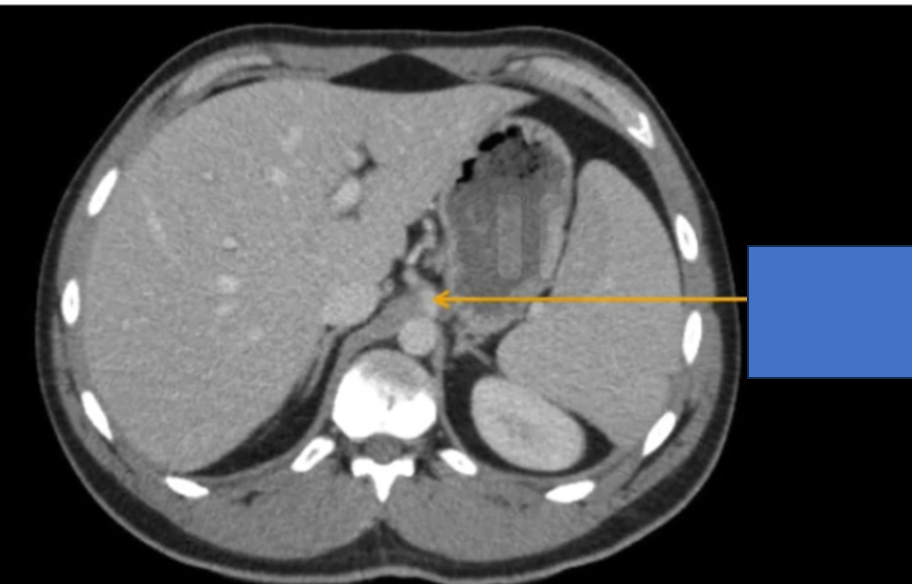

đm thận T?